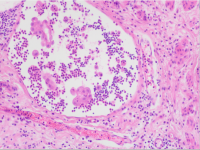

2017年第04期(总第123期)——双侧腹股沟淋巴结肿大